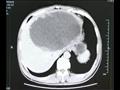

وذهب "شاي" إلى المستشفى بعد أربعة أشهر، عقب معاناته من قشعريرة وحمى شديدة لمدة ثلاثة أيام. وذهل الأطباء عندما اكتشفوا أن كبد المريض يحتوي على كتلة ضخمة مليئة بالصديد يبلغ طولها 19 سم وعرضها 18 سم، وفقا للتقرير.

وحاول الجراحون في البداية تقليل النتوء الاجتياحي مثل الكيس، عن طريق تجفيف الكتلة من السوائل، ولكنهم أدركوا بسرعة أن العدوى شديدة جدا، وقرروا قطع نصف الكبد.

وكشف فحص لاحق أن الكتلة كانت تحتوي على عدد لا يحصى من البيض الذي وضعه متفرع الخصية الصيني أو وشيعة الكبد الصينية، وهو طفيل موجود في المأكولات البحرية النيئة.